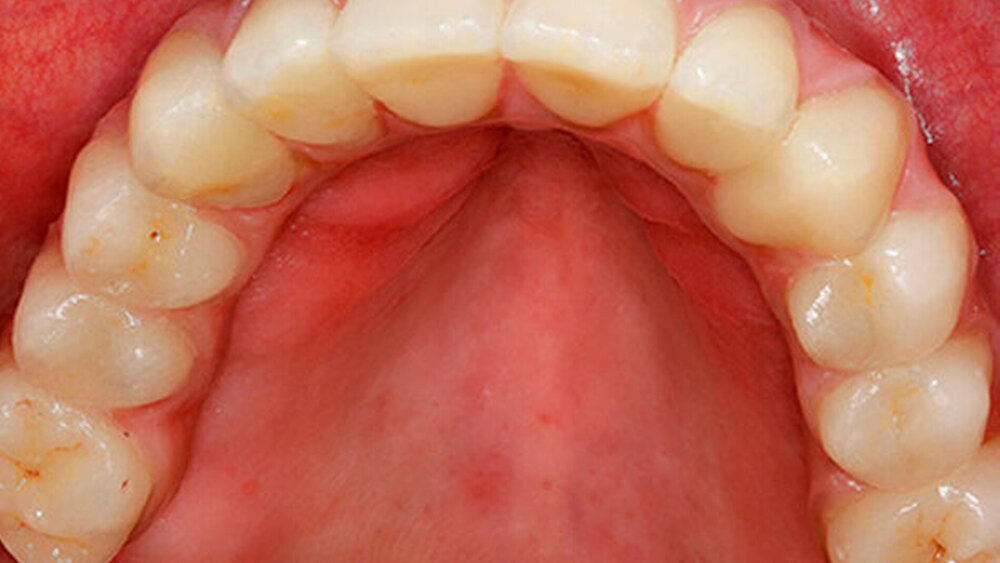

Bei Interimsversorgungen bis zur Osseointegration und der sich anschließenden prothetischen Phase (etwa drei bis vier Monate). Werden die inserierten und freigelegten Implantate mit einem Langzeitprovisorium versorgt, bleibt dieses bis zur Adaptation sechs bis acht Monate in situ. Bis der All-on-four-Patient sein verschraubtes Provisorium richtig adaptiert hat, vergehen auch fünf bis sechs Monate. Die Dauer des Provisoriumtragens unterscheidet sich also nicht wesentlich.

Eine 67 Jahre alte Patientin stellte sich mit dem Wunsch einer Oberkiefersanierung in unserer Praxis vor. Ihre Restzähne waren aufgrund von Parodontitis und funktioneller Überlastung nicht mehr erhaltungswürdig. Wir ließen sie bis kurz vor der definitiven Versorgung als strategische Pfeilerzähne für die Interimsprothese in situ.

Nein, aber das ist möglich. ZTM Stefan Picha hat die prothetische Versorgung übernommen.